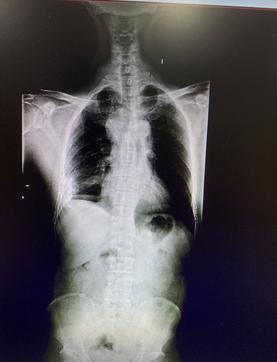

· 另外,久坐会使得腰部出现慢性疲劳而发生不同程度的疼痛感。长此以往,容易导致腰椎的侧弯或者椎体旋转,形成恶性循环。

男性,49岁(脊柱全长正位片)

· 有一些中老年人腰椎伴有不同程度的退行性变或者伴有腰椎间盘突出,而在患有腰椎间盘突出时长时间久坐会让腰部长时间承受上半身的重量,就容易导致腰椎间盘的纤维环被破坏而压迫到神经,也就会出现腰部疼痛的现象。